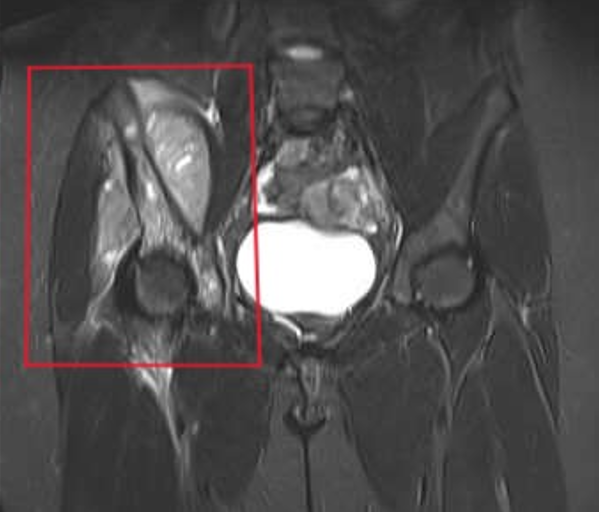

Unseen Battles: Exploring Ewing Sarcoma Through Science and Storytelling

“Not all cancers wear a pink ribbon.”This was the line that opened my presentation on Ewing Sarcoma, a rare and aggressive bone cancer that predominantly affects children and adolescents. As part of an academic seminar I helped organize for our Biomedical Science class, we explored different rare diseases and presented them from multiple angles — pathology, treatment, patient experience and research gaps. I chose Ewing Sarcoma not just for its medical complexity, but for the silence that often s...